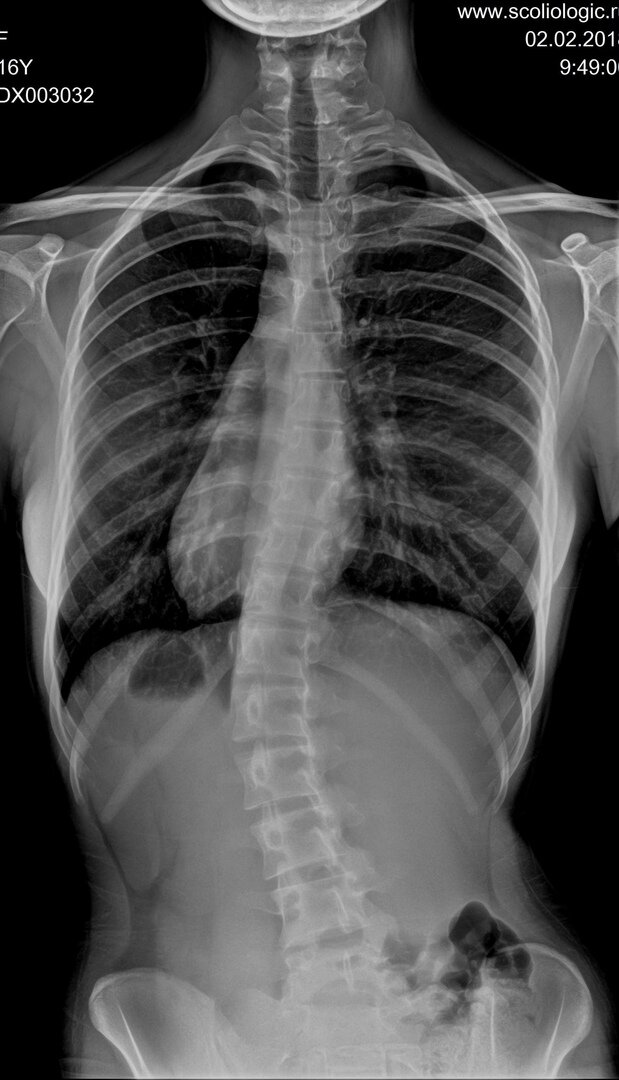

Точный диагноз при сколиозе можно поставить только по рентгену.

Фотохимическое воздействие ионизирующих лучей позволяет создавать информативные, с диагностической точки зрения, снимки. При прохождении сквозь человеческое тело рентгеновские лучи проецируются на пленке. На снимках лучше всего видны кости – ярко-белого цвета. Это связано с тем, что кальций больше всего поглощает рентгеновские лучи.

Рентген - первое, что нужно сделать, услышав диагноз "сколиоз".